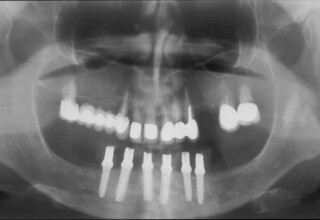

Full mouth prosthetic reconstruction on implants with a different approach on upper and lower jaw

Lower jaw: extractions, direct implant placement and immediate loading (same day) with a transitional bridge.

Upper jaw: Sequential extractions, sequential implant placement and gradual incorporation in the temporary bridge so that the patient was never left without fixed teeth. The aim of the above approach was to have the patient in continuous functional and aesthetic reconstruction, without immediate loading due to anatomical restrictions. Old smiling photos of the patient were used because the natural shape of the teeth was completely lost due to repetitive prosthetic attempts. Tooth relationship and teeth-lip support was transferred to the temporary restorations. Two different transitional bridges were needed to fully estimate phonetics, mastication and esthetics. After the necessary adjustments were finalized, the temporary bridge was used as a guide for the permanent bridges.

Final